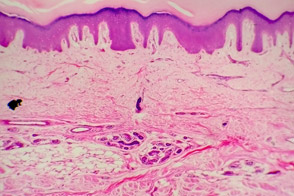

2. Proliferative Phase: Fibroblasts are stimulated to synthesize collagen and form granulation tissue. This new tissue is fueled by the growth of new blood vessels through a process called angiogenesis.

3. Remodeling phase: This phase is characterized by the re-epithelialization that reconstructs the tissue. The new layer covers the injured skin and allows the repair process to continue. At this stage, the new tissue is put and practically restores the whole condition of the original tissue.

When an injury cannot fully escalate into re-epithelialization, external support is needed to facilitate the biochemical and cellular processes that are impaired. In this sense, external supports, such as topical medications, bandages, dressings and others, must show characteristics such as: (a) preservation of cellular activity at each stage, (b) constant maintenance of an appropriate physiological condition on the lesion, (c) promotion of microcirculation and satisfactory gas exchange, (d) inhibition of the extracellular matrix disruption, and (e) promotion of the synthesis of tissue growth factors. When a topical medication or a dressing does not enable on of these processes, the wound healing is compromised and results in a chronic lesion.

Some dressings that occlude the lesion and squeeze the peripheral circulation, stopping the exchange of oxygen in the healing tissue, are responsible for the failure of the treatment, and also stimulate the spreading of pathogens such as bacteria and fungi. The lack of oxygen in the tissue impairs the action of the macrophages and other important cells in the healing process. Other topical medications that have oxidant components in their formulations seriously harm the tissue repairing process, for the cytotoxic acts over the immunocompetent cells such as macrophages, which play a fundamental role on the coordination of the healing processes.